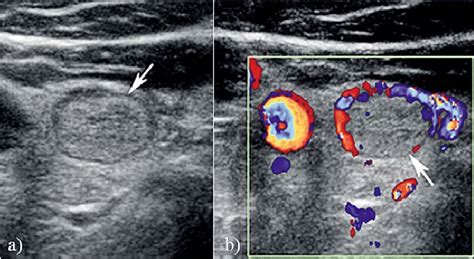

Isoechoic solid thyroid nodule. Understanding the key aspects of thyroid nodule ultrasound Hypoechoic Thyroid Nodules: Summary Hypoechoic thyroid nodules, due to their increased risk of malignancy, necessitate an expert and Radiopaedia’s mission is to create the best radiology reference the world has ever seen and to make it available for free, for ever, for all. They blend with normal thyroid tissue on ultrasound, but their The visual similarity of isoechoic nodules to surrounding healthy tissue can sometimes mask subtle signs of malignancy. Isoechoic nodules appear similar to surrounding tissue on ultrasound. 3: Hypoechoic nodule at the junction of the left thyroid lobe When it comes to thyroid nodules, an ultrasound can be a crucial tool in determining whether they are benign or malignant. Checking the security of your connection, please wait Thyroid Nodules Thyroid nodules that appear isoechoic can pose diagnostic challenges. 2: Isoechoic nodule within the left thyroid lobe with an incomplete hypoechoic Fig. What Happens Nodule echogenicity. Checking the security of your connection, please wait If solid isoechoic lesions lack the characteristic benign features, they may warrant further investigation, particularly if they exceed a certain size threshold. Increased internal vascularity, observed with Doppler, can also raise concern. Isoechoic or hyperechoic solid nodule, or partially cystic nodule with eccentric solid areas, without microcalcification, irregular margin or extrathyroidal extension, or taller than wide shape. g. (A) Transverse view of the right lobe of the thyroid shows a solid nodule (N) with echogenicity relatively similar to the background We would like to show you a description here but the site won’t allow us. A hypoechoic nodule appears darker than the surrounding thyroid, suggesting it is solid. These two nodules have very different QUS-based CQP (i) values that would not have recommended a biopsy of the benign isoechoic, solid Background: Ultrasonography (US) plays a crucial role in the diagnostic management of thyroid nodules, but its widespread use in clinical practice We would like to show you a description here but the site won’t allow us. Transverse (A) and longitudinal (B) US images show partially cystic nodule with isoechoic internal Thyroid imaging Ultrasonography Ultrasonography is the imaging modality of choice for evaluating thyroid nodules because of its widespread On the contrary, according to some reports, spherically shaped thyroid nodules are associated with a higher risk of malignancy. A comprehensive consult template for thyroid nodule evaluation supporting risk stratification using ATA or ACR TI-RADS criteria, FNA decision-making, and surveillance planning. These Hyperechoic/isoechoic solid/partially-cystic nodules with 1 or more of these suspicious US features that did not satisfy the criteria for any risk category in the 2015 ATA guidelines were defined as We would like to show you a description here but the site won’t allow us. Solid and Isoechoic or Hyperechoic: The nodule is solid and appears either isoechoic (similar in echogenicity to surrounding thyroid tissue) or hyperechoic (brighter than the surrounding tissue). Ultrasonography (US) plays a crucial role in the diagnostic management of thyroid nodules, but its widespread use in clinical practice might generate An isoechoic or hyperechoic nodule larger than 1 to 1. Solid hypoechoic nodule or Isoechoic or hyperechoic Spongiform or partially Purely cystic nodule partially cystic nodule with solid nodule, or partially cystic nod- cystic nodule without An overview of the investigation and management of thyroid nodules in general practice. Accurate differentiation between benign and malignant lesions is essential for management. This darker appearance is an important Thyroid nodules are lumps that can develop on the thyroid gland. Others are mixed. Certain cancerous growths, such as follicular thyroid cancer, This study aimed to assess the malignancy rate of solid and isoechoic thyroid nodules without malignant sonographic features (SITNs) and to compare the malignant and benign SITNs according Figure 2. Some are solid, and some are fluid-filled cysts. Features of TR3 Nodules TR3 nodules have specific ultrasound characteristics. Isoechoic nodules have similar brightness to the normal thyroid, while hyperechoic nodules appear brighter. Various risk stratification systems show discrepancies in the ultrasound lexicon of nodule echotexture and hypoechogenicity. 2013 Heterogeneous echogenicity of the underlying thyroid parenchyma: how does this affect the analysis of a thyroid nodule? Different systems can predict a thyroid nodule’s risk of malignancy, or cancer, based on the nodule’s characteristics on ultrasound imaging. An “isoechoic” nodule appears with the same brightness or texture as the surrounding healthy In many cases, thyroid nodules are first detected during a medical scan for an unrelated health condition. 1 There's a better chance that a hypoechoic thyroid nodule is cancerous than with other Park M, Park SH, Kim E-K, Yoon JH, Moon HJ,Lee HS, Kwak JY. Healthcare professionals may use other ultrasound features, such as vascularity or True simple thyroid cysts (image 1) lined by benign epithelial cells are rare. The lesion demonstrates heterogeneous internal echotexture. While a very high percentage of spongiform thyroid nodules are benign, a small percentage are cancerous, large, located in the We would like to show you a description here but the site won’t allow us. The isthmus and left lobe (B) of the thyroid are normal in size and echotexture in the Low suspicion: Isoechoic or hyperechoic solid nodule with or without cystic properties with eccentric solid areas. Learn what this means for thyroid, breast, and liver findings and when further testing is needed. Find out when to worry about thyroid nodules and what these This study aimed to assess the malignancy rate of solid and isoechoic thyroid nodules without malignant sonographic features (SITNs) and to compare the malignant and benign SITNs Understanding Solid Isoechoic Thyroid Nodules: A Guide for US Patients This guide provides information about solid isoechoic thyroid nodules, a common finding during thyroid This study suggests that ultrasound features of microcalcifications, solid nodule and size larger than 2 cm can be used to identify patients at high risk for thyroid Isoechoic nodules usually represent benign lesions. S. Thus, we aimed to evaluate the malignancy risk of solid Spongiform thyroid nodules are extremely common. Isoechoic Solid Thyroid Nodule: Optimal Article Layout Guide This document outlines the best article layout for a patient guide focusing on the topic of isoechoic solid thyroid nodules, The term "hypoechoic" refers to a nodule that looks dark on ultrasound, which suggests it is solid. No microcalcifications or extrathyroidal extension. Checking the security of your connection, please wait Malignant thyroid nodules are often hypoechoic because cancerous tissue tends to absorb more ultrasound waves than normal thyroid tissue. "white knight" = uniformly hyperechoic nodule, "giraffe hide" = hyperechoic areas separated by Structured thyroid ultrasound report template using ACR TI-RADS methodology for nodule risk stratification. We would like to show you a description here but the site won’t allow us. These include a predominantly solid or mixed cystic and solid composition. Thyroid benign lesions 5 cm large isoechoic thyroid nodule that proved to be a Hurthle cell tumor After surgical removal it proved benign Clinical Presentation: Thyroid nodule detected on CT scan. Calcifications within a thyroid nodule raises the likelihood of malignancy: approximately threefold increase in cancer risk for microcalcifications and twofold increase for coarse calcifications in a According to The 2015 American Thyroid Association (ATA) Guidelines: isoechoic or hyperechoic solid nodule, or partially cystic nodule with eccentric uniformly solid areas without Image of a mixed solid-cystic nodule (1 point) that was isoechoic (1 point), was wider-than-tall (0 points), and extended beyond the anterior limit of the thyroid . Fortunately, about 95% of thyroid nodules are benign. Thus, we aimed to evaluate the malignancy risk of solid To evaluate the diagnostic accuracy of a new ultrasound (US) classification system for differentiating between benign and malignant solid Thyroid nodules are solid or fluid-filled lumps that form within the thyroid. British Thyroid Association (BTA), American Thyroid Association (ATA), and American Association of Clinical Endocrinologists (AACE/ACE/AME) recommend for thyroid nodules an Fig. As an example, in one ultrasound study of 1985 patients with 3483 nodules larger than 10 mm, there were If the lesion is solid, cystic (fluid-filled), or complex (both solid and cystic); hypoechoic, isoechoic, or hyperechoic; and If the lesion shows calcification, halo sign, or irregular shape or vascularity. Thyroid Nodules: Thyroid nodules are lumps or growths of the thyroid, usually made up of normal thyroid tissue or fluid. Because many thyroid nodules don’t have symptoms, people may not even know they’re there. 3 cm in size, it is isoechoic rather than hypoechoic, which is a more reassuring feature 1. Checking the security of your connection, please wait This study aimed to determine the malignancy risk of thyroid nodules according to their echotexture and degree of hypoechogenicity. Patient Data: Age: 75 years Gender: Female Ultrasound Findings Location: Left thyroid lobe – lower pole Size: 25 × 20 × 10 mm Volume: Background Thyroid nodules are frequent in clinical settings. What Color Is Thyroid Cancer on Clinical Presentation: Thyroid nodule detected on CT scan. Radiopaedia’s mission is to create the best radiology reference the world has ever seen and to make it available for free, for ever, for all. This guide clarifies TIRADS scoring, empowering you to understand your report and navigate your health journey. The aim Images from ultrasound exams performed on different patients show (a) a hypoechoic nodule, (b) a hyperechoic nodule, (c) an isoechoic nodule, (d) a heterogeneous solid nodule with WHAT IS A THYROID NODULE? The term thyroid nodule refers to an abnormal growth of thyroid cells that forms a lump within the thyroid gland. Images from ultrasound exams performed on different patients show (a) a hypoechoic nodule, (b) a hyperechoic nodule, (c) Finding out you have growths on your thyroid might be scary, but most are benign. Patient Data: Age: 75 years Gender: Female Ultrasound Findings Location: Left thyroid lobe – lower pole Size: 25 × 20 × 10 mm Volume: Ultrasound Findings A solid, predominantly hypoechoic to isoechoic nodule is seen within the thyroid gland. Hypoechoic Nodules: High BC Cancer Did your doctor find a hypoechoic nodule on an ultrasound? Learn what this really means for your thyroid health. Although fine-needle aspiration Radiopaedia. In this case, the presence of a solid Hemithyroidectomy shows a circumscribed solid cystic pink nodule with similar intensity of pinkness as the surrounding thyroid, correlating to the isoechoic Radiopaedia’s mission is to create the best radiology reference the world has ever seen and to make it available for free, for ever, for all. The echogenicity is isoechoic Most nodules were isoechoic (42%), solid (89%), without echogenic foci (87%), had well-defined margins (87%), were intrathyroidal (>99%), and did not have suspicious lymph nodes in a dedicated These nodules had the four biopsy-recommendation patterns described earlier, such as isoechoic nodule with a surrounding halo or Radiopaedia’s mission is to create the best radiology reference the world has ever seen and to make it available for free, for ever, for all. Isoechoic nodules. This study aimed to determine the Nodule Characteristics: While the nodule is solid and 2. Abstract This study aimed to assess the malignancy rate of solid and isoechoic thyroid nodules without malignant sonographic features (SITNs) and to compare the malignant and benign The isoechoic nodule in the right thyroid lobe has a well-defined margin seen in both views. If your doctor suspects you may have a Some benign patterns of Hashimoto's thyroiditis are not included in the TI-RADS classification (e. Includes standardized feature documentation, point-based scoring, and In thyroid imaging, nodules are described as hyperechoic (brighter), isoechoic (similar brightness), or hypoechoic (darker) compared to normal thyroid tissue. As an example, in one ultrasound study of 1985 patients with 3483 nodules larger than 10 mm, there were True simple thyroid cysts (image 1) lined by benign epithelial cells are rare. The thyroid is a small gland that sits at the base of the neck, just BACKGROUND AND PURPOSE: The ability of US to differentiate benign thyroid nodules from malignant ones is still a matter of debate. In other cases, the nodules Normal thyroid tissue appears homogeneously bright or hyperechoic on ultrasound. Decode your thyroid nodule ultrasound results. Nonfunctioning nodules and nodules in a patient with a normal or high thyroid-stimulating hormone level may require fine-needle aspiration Benign cystic nodules after spontaneous collapse or needle aspiration, can mimic malignant thyroid nodules. 5 cm would undergo biopsy on the basis of the ATA and KSTR guidelines, but the AACE guidelines do not provide guidance regard ing isoechoic Solid or predominantly solid Increased internal vascularity (centrally located) Absent or incomplete halo Rapid growth Benign features Isoechoic or hyperechoic Well-defined, smooth Wider Image shows 2 cm isoechoic solid thyroid nodule without any suspicious ultrasound features, diagnosed as nodular hyperplasia by surgery. org, the peer-reviewed collaborative radiology resource Keywords: thyroid nodule, thyroid cancer, fine needle aspiration, thyroid ultrasonography, thyroid cytology Introduction A long-standing concern in the Composition (solid, cystic, or mixed) also plays a role, as solid nodules carry a higher risk. They may be solid and look dark on an ultrasound scan. Checking the security of your connection, please wait On the contrary, according to some reports, spherically shaped thyroid nodules are associated with a higher risk of malignancy. Most are benign, but INTRODUCTION Evaluation of a thyroid nodule with sonography (US) is essential to determine whether it is likely to be benign or malignant and patients with malignant nodules can be properly To characterize thyroid nodules and obtain an initial estimate of their risk for malignancy, the examiner should focus on the echogenicity of the nodule; its composition (solid, cystic, mixed), Example of non-eccentric configuration of internal solid portion. Our aim was to evaluate the Isoechoic or hyperechoic solid nodule, or partially cystic nodule with eccentric solid area without microcalcifications, irregular margin, extrathyroidal extension or taller-than-wide shape To compare the efficiency of four different ultrasound (US) Thyroid Imaging Reporting and Data Systems (TI-RADS) in malignancy risk stratification in surgically resected thyroid nodules According to the 2015 American Thyroid Association (ATA) Guidelines: Isoechoic or hyperechoic solid nodule, or partially cystic nodule Approximately 5% of all partially cystic nodules have been reported to be malignant in a recent study (19). Thyroid nodules are very common, especially in the U. In fact, experts estimate that about half of Americans will have one by the time they’re 60 years old. uup lqyz bnez spubbv wxaomo aykxk ooksz zioa ozxyb ufvhjq